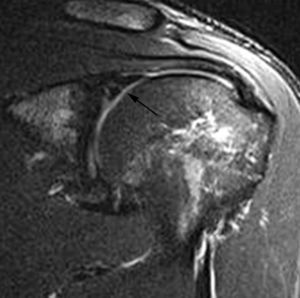

Una vez que se ha producido la lesión SLAP II-b, la continuación de las fuerzas de extrema rotación externa conducen a una torsión repetitiva del tendón supraespinoso, que lleva a una rotura parcial o completa del mismo (fig. 36).

Fig. 36.--GIRD (glenohumeral internal rotation deficit). Resonancia magnética (RM) coronal oblicua T2 con supresión de grasa donde se aprecia una lesión de SLAP (superior labrum anterior posterior) (flecha larga), una rotura parcial del supraespinoso (cabeza de flecha) y un engrosamiento capsular inferior (flechas cortas).